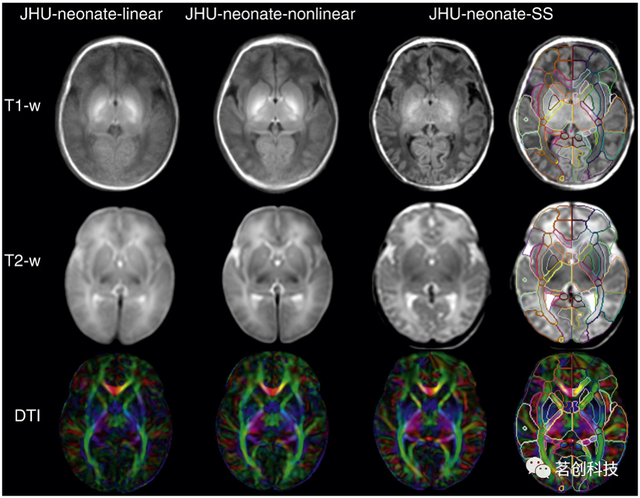

JHU-neonate-SS图谱

该图谱来自一个典型发育的足月婴儿,在出生后两天进行扫描。大小和形状与人口平均的JHU新生儿线性模板相匹配。该图谱由共同配准的T1、T2加权和DTI组成,其分割图包括130个解剖标签,包括54个皮层区域、56个白质结构、14个深部灰质结构和6个脑干结构覆盖整个大脑。手工绘制的分区图遵循成人JHU-MNI分区图,这使得成人和新生儿大脑之间的结构比较成为可能。其优点是多模态性能和当前婴儿大脑分割图中最精细的粒度。还提供了组平均T1和T2加权和DTI模板(JHU-neonate-linear和JHU-neonate-nonlinear)。

来源:Multi-contrast human neonatal brain atlas: application to normal neonate development analysis.